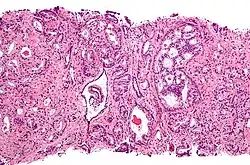

Gleason pattern 4. H&E stain.

Gleason 4

Gleason pattern 4 glands are no longer single/separated glands like those seen in patterns 1–3. They look fused together, difficult to distinguish, with rare lumen formation vs Gleason 1–3 which usually all have open lumens (spaces) within the glands, or can be cribriform-(resembling the cribriform plate/similar to a sieve: an item with many perforations). Fused glands are chains, nests, or groups of glands that are no longer entirely separated by stroma-(connective tissue that normally separates individual glands in this case). Fused glands contain occasional stroma giving the appearance of "partial" separation of the glands. Due to this partial separation, fused glands sometimes have a scalloped (think looking at a slice of bread with bite taken out of it) appearance at their edges.[4][7]